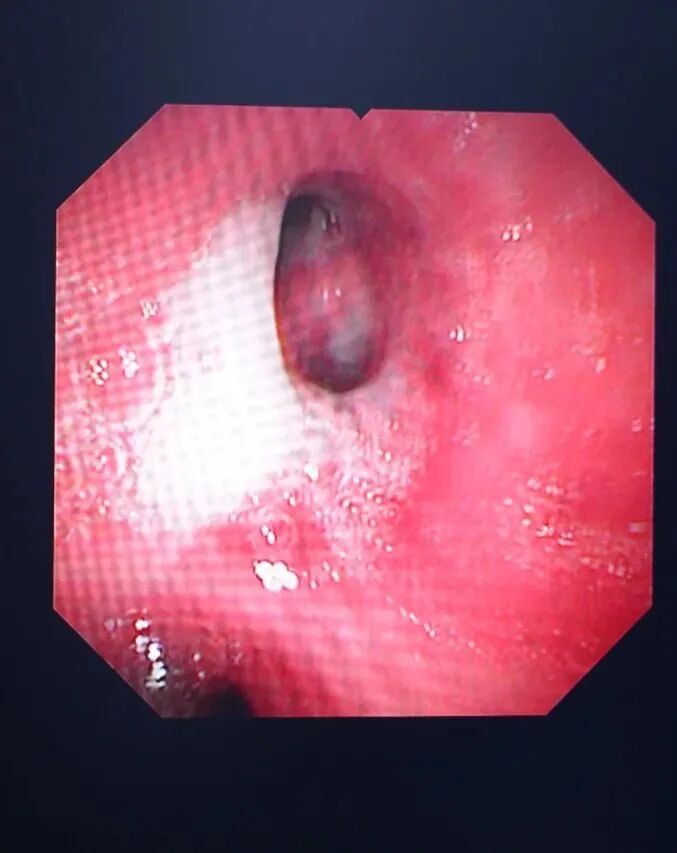

清理气管分泌物

支气管镜检查就是将细长的支气管镜经口或鼻置入患者的下呼吸道,医生可以直观地观察到气管和支气管病变,并根据病变做出判断。是呼吸系统疾病临床诊断和治疗的重要手段,临床应用广泛。